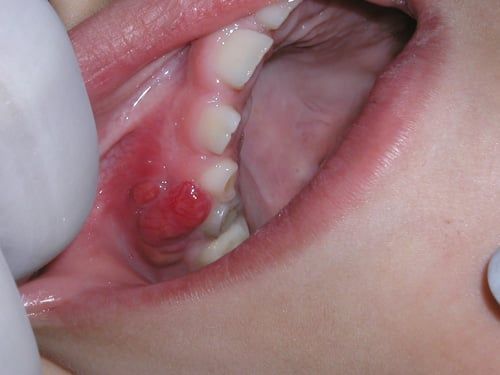

Mucocele

This is a common benign lesion in children and adolescents that results from the rupture of the excretory ducts (very small tubes) that deliver saliva to the top tissues of the lips. More than 75% of mucocele are located on the lower lip and their size and color may vary, however, they tend to be relatively painless for the most part. Most of the time, patients report that these "bumps" grow until they burst spontaneously, leaving small ulcers that heal within a few days. This does not mean the lesion is gone, as they often tend to re-appear weeks or months later. Most dentists will recommend surgical treatment for these lesions.